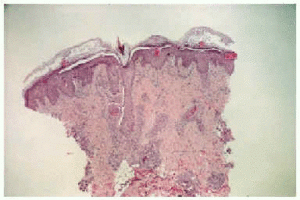

Cinco días después del final de la radioterapia la niña es hospitalizada por neutropenia febril con foco respiratorio, iniciándose tratamiento con cefepime y codeína. Al día siguiente se observó la aparición de unas placas eritematovioláceas, conformadas por micropápulas no foliculares, distribuidas en la región lumbar y en la zona del abdomen, con predilección por los bordes de la cicatriz de laparotomía (figs. 1 y 2). En el estudio histopatológico se evidenció una metaplasia escamosa madura de las porciones rectas de los conductos de las glándulas ecrinas sin afectación de los ovillos (fig. 3). Se observaban asimismo frecuentes células necróticas, queratinización de las luces y aislados queratogranulomas que entraban en contacto con la luz glandular (figs. 4 y 5). El diagnóstico histológico fue de siringometaplasia escamosa ecrina. La enferma continuó tratamiento quimioterápico, a pesar de lo cual las lesiones evolucionaron espontáneamente hacia la curación en un período aproximado de 1 mes, quedando una hiperpigmentación residual que se fue borrando paulatinamente.

Fig. 1.--Micropápulas en cicatriz de laparotomía y zonas de radioterapia previa.

Fig. 2.--Detalle de las lesiones.